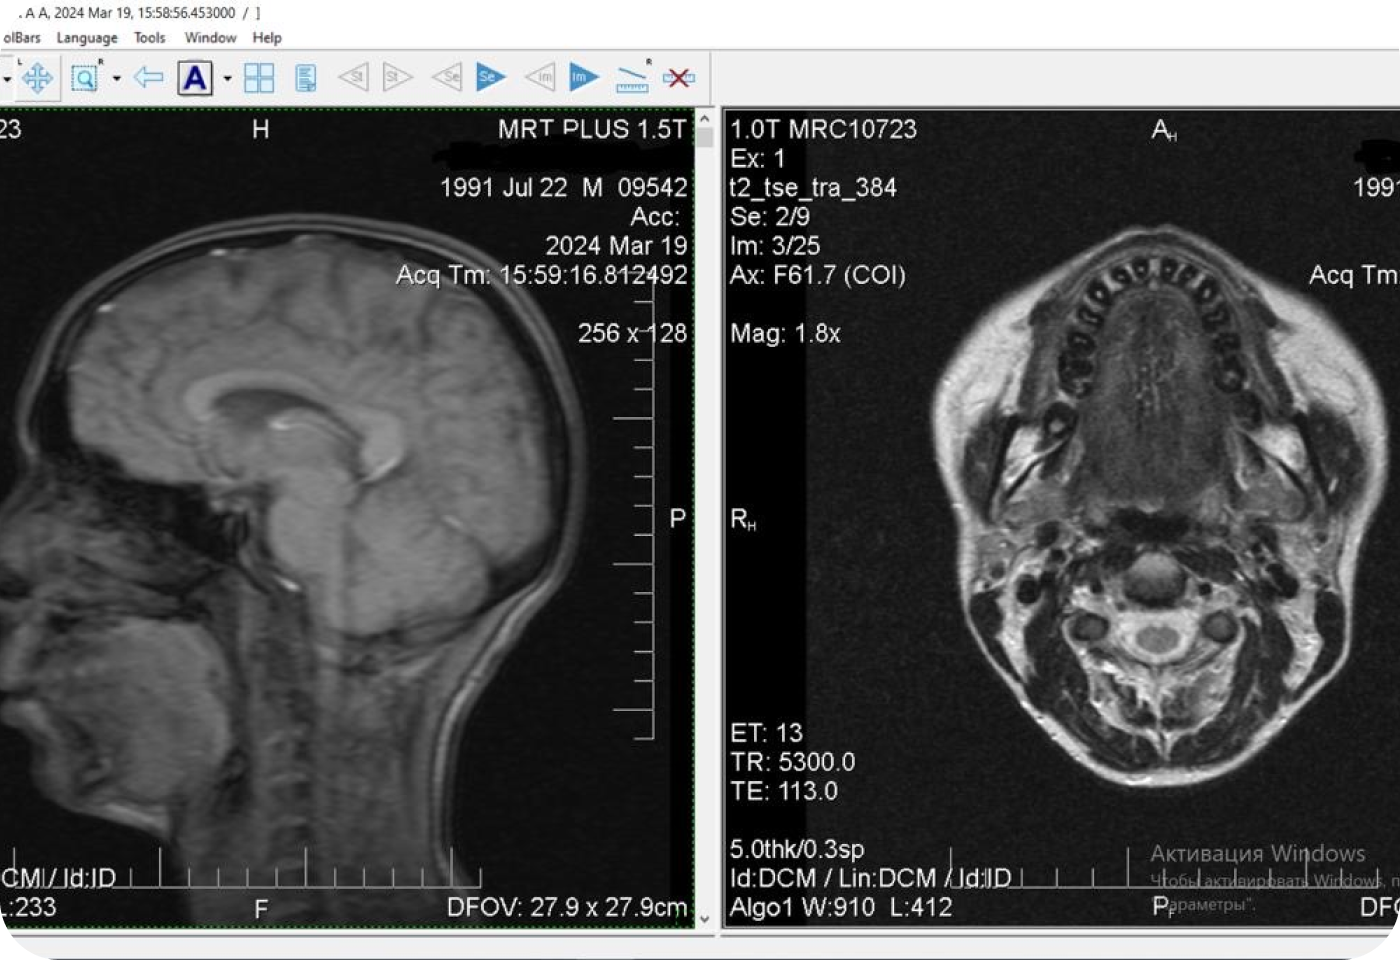

Перед началом лечения я провожу часовую первичную консультацию. Для этой встречи вам необходимо сделать «МРТ ВНЧС» и «КЛКТ двух челюстей с захватом ВНЧС в привычном прикусе».

Во время консультации мы смотрим и анализируем ваши исследования. Я подробно объясняю строение ВНЧС, показываю все причинные факторы вашей проблемы, отвечаю на все вопросы «Почему?»